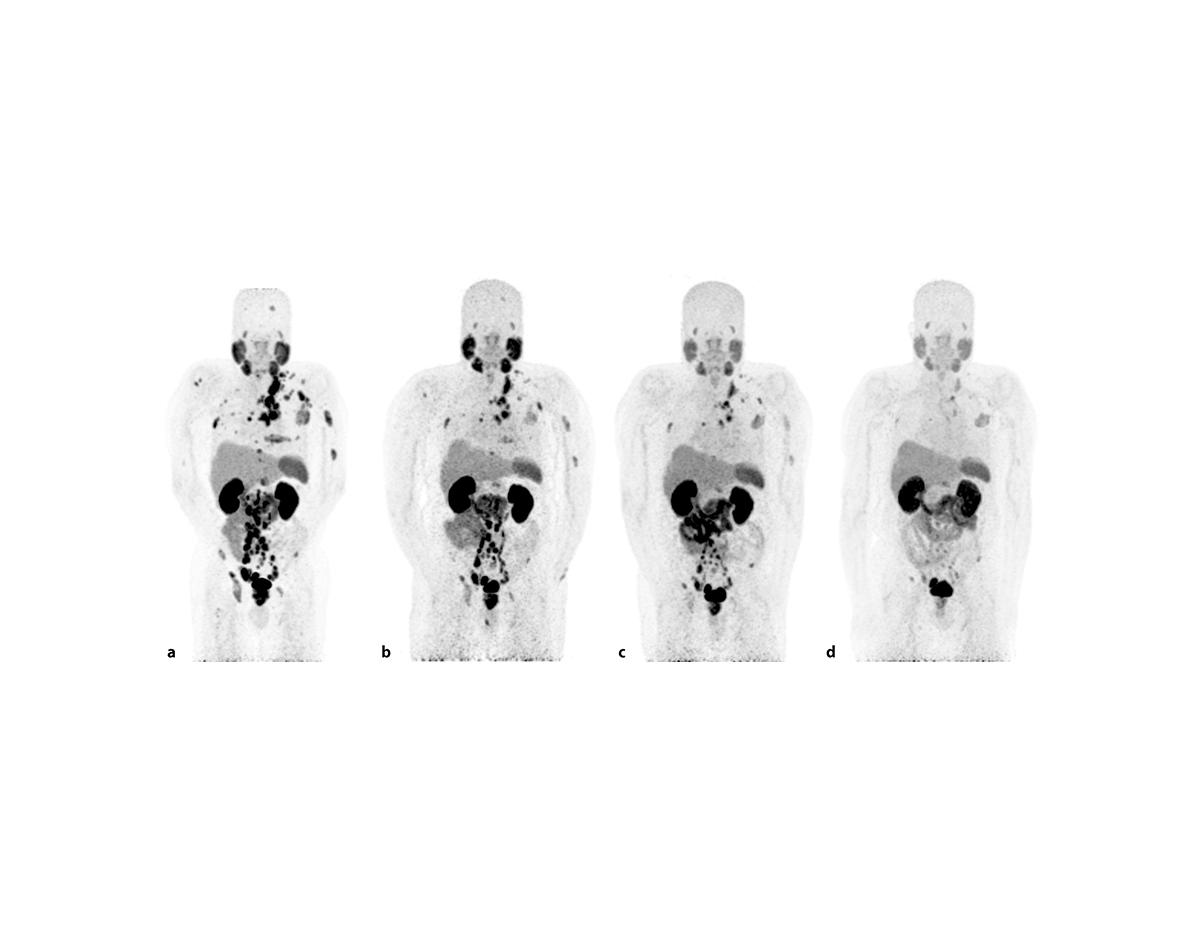

Tomografía por emisión de positrones (TEP) del antígeno prostático específico de membrana (PSMA) de un hombre con cáncer de próstata (a) al inicio del tratamiento con Lu177-PSMA-617 y (d) después de 6 ciclos de la terapia. Fuente: Tijdschrift voor Urologie.